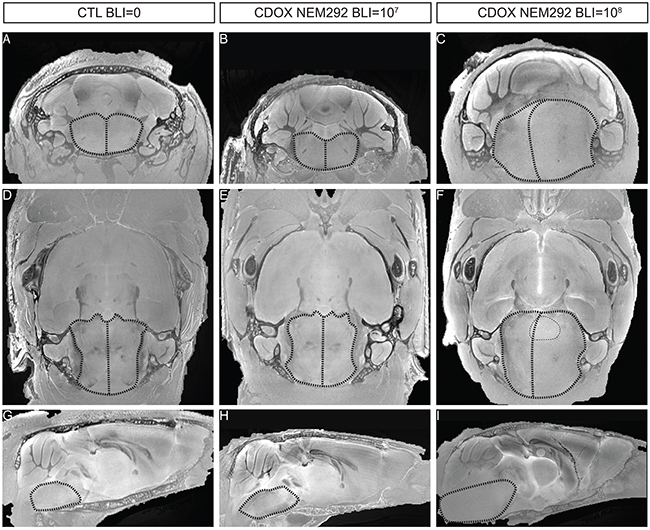

We finally investigated how MR-imaging modalities of DIPG were recapitulated in CDOX models. Indeed, T2-weighted MRI is one of the only non-invasive methods for DIPG diagnosis, showing an infiltration respecting the pontine fiber tracts and an inflated brainstem in patients. We performed ex-vivo T2-RARE (Rapid Acquisition with Relaxation Enhancement) MR acquisition at 11.7 Tesla in 3 different animals: the first showing an intermediate bioluminescence radiance signal at 107 (28 days post-graft), the second in a mouse reaching 108 (77 days post-graft) that we characterized as advanced stage of the disease, and a last non-injected control mouse. Only anatomical changes were observed due to the highly infiltrative nature of the tumor with a shift of the midline to the left in coronal and axial view, much more pronounced in the 108 BLI-positive mouse than in the 107 (Figure 6C, 6F vs. 6B, 6E). The inflation of the pons was also more prominent at higher BLI signal on sagittal panels (Figure 6H vs. 6I). We also noticed a slight hyperintensity in the right side of the brainstem corresponding to the site of injection on the axial panel (Figure 6F).

Figure 6: T2-sequence MRI modalities of DIPG are recapitulated in the brainstem of end-stage CDOX models. Anisotropic T2-sequence MR-Imaging at 11.2T of a non-grafted control mouse A, D, and G., CDOX NEM292 showing a 107 BLI level B, E, and H. and CDOX NEM292 showing a 108 BLI level C, F, and I. For visualization, images were focalized on the pons according to the coronal plane A, B, and C., the axial plane D, E, and F. and the sagittal plane G, H, and I. sections. Anatomical changes with a midline shift and pons hypertrophy were observed for the 108 BLI mouse only. A hyperintensity could also be observed in the pontine region (highlighted with dots in F). Brainstem and midline are depicted by dashed lines.